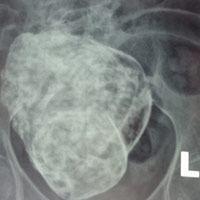

Thế giới chỉ ghi nhận 300 trường hợp Bác sỹ CKII Lê Quang Vinh cũng cho biết thêm, bình thường khi thai bị chết lưu sẽ tìm cách tự đào thải ra khỏi cơ thể mẹ hoặc bằng các biện pháp nạo hút, bác sĩ sẽ lấy thai lưu ra ngoài. Trong trường hợp này, cụ già 76 tuổi đã qua tuổi sinh sản từ lâu, vì thế việc phát hiện thai nhi bị vôi hóa phải qua các xét nghiệm và chẩn đoán hình ảnh. Ðây là ca bệnh hiếm gặp, y văn thế giới mới phát hiện khoảng 300 trường hợp. Ở ca bệnh đặc biệt này, các bác sĩ sẽ thăm khám, làm các xét nghiệm cần thiết và quan trọng nhất là tùy vào tình hình thể trạng của bệnh nhân để có cách xử trí thích hợp. |

Ngày bà nhập viện Đa khoa Cam Ranh, các bác sĩ chẩn đoán cơn đau bụng âm ỉ của bà bắt nguồn từ cái bào thai đã hóa thạch. Hôm đó, ngồi trong phòng khám “nuốt” từng lời bác sĩ, bà Thập thấy chẳng khác nào sét đánh ngang tai. Thì ra gần 30 năm đằng đẵng vừa qua, bà mâng trong người một mầm sống. Bà Thập cười cho biết: “Lúc chồng tôi còn sống, chúng tôi vẫn “nồng nàn” với nhau lắm. Nếu theo các y bác sỹ thông báo thì hồi ấy tôi thụ thai cũng đã suýt soát 50 tuổi rồi. Ở cái tuổi ấy mà vẫn có thai được thì cũng là chuyện lạ! Kỳ lạ hơn nữa là suốt mấy chục năm qua, nó vẫn ở trong người tôi mà tôi không hề hay biết gì!”

Trên thế giới cũng từng có trường hợp như thế, chứ đâu phải chỉ riêng mẹ tôi”. Người dân trong vùng rất tò mò và muốn thử một lần nhìn thấy thai đá cho biết. “Đời tôi chưa từng nghe nói đến chuyện thai đá bao giờ và cũng càng chưa từng nghĩ đến chuyện bà Thập lại mang thai đá, tôi rất muốn nhìn xem thai đá trông ra sao? Không có ý gì xấu mà chỉ thấy hiện tượng đặc biệt hiếm gặp thôi!”, một người đàn ông trong bệnh viện bày tỏ. Không giống với các thai phụ khác, theo dự đoán, sau khi “chào đời” thai nhi của bà Thập sẽ giống một tảng đá có hình người, dù kích cỡ không lớn lắm.

Trên thực tế có những trường hợp thai chết lưu không tìm thấy nguyên nhân, nhưng y học ngày nay đã biết nhiều nguyên nhân gây ra thai chết lưu. Với những thai phụ tuổi cao trên 40 tuổi, tỉ lệ này cao gấp 5 lần so với nhóm những người mẹ dưới 40 tuổi. Việc bà Thập còn thụ thai được ở độ tuổi 50 cũng là một điều ít gặp. Thêm nữa, việc thai đá này không làm ảnh hưởng tới sức khỏe, cũng như vận động, và bà không hề hay biết sau từng ấy năm quả là một sự kiện hy hữu của y văn. Sau sự việc hi hữu này, bà Thập chỉ mong muốn các y bác sỹ sớm tiến hành giải quyết bào thai đá này, để sức khỏe của bà được ổn định, cũng như tâm lý không còn lo sợ nữa.